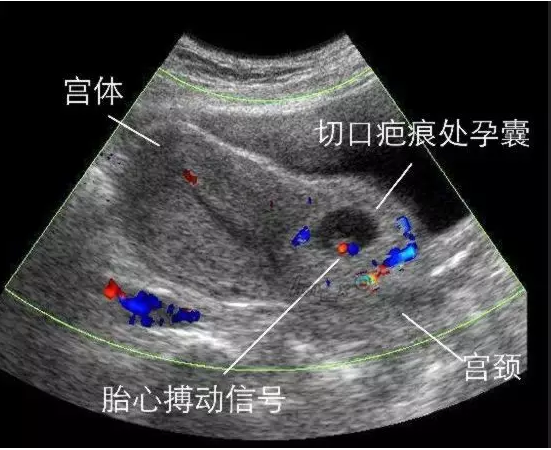

主诉状况:意外怀孕,停经40天,因阴道淋漓出血来院就诊,B超提示考虑瘢痕妊娠

术前诊断:1、早孕 2、疤痕子宫 3、疤痕妊娠Ⅲ型

子宫瘢痕处妊娠是较难处理的异位妊娠,也是妇产科医师较为头疼的问题之一。通俗来讲是受精卵通过剖腹产后瘢痕组织的裂缝或窦道,侵入瘢痕内并在肌层种植,持续生长,所形成绒毛与子宫肌层黏连,甚至穿透子宫壁。医学治疗上不仅要干净清除掉妊娠囊,还需要修复瘢痕缺损,预防子宫大出血、失血性休克及二次复发是关键。

同时见孕囊向肌壁间和膀胱部位生长,子宫原切口瘢痕处薄弱,并向外膨出,遂进行:双侧子宫动脉结扎术+瘢痕妊娠切开取胚术。